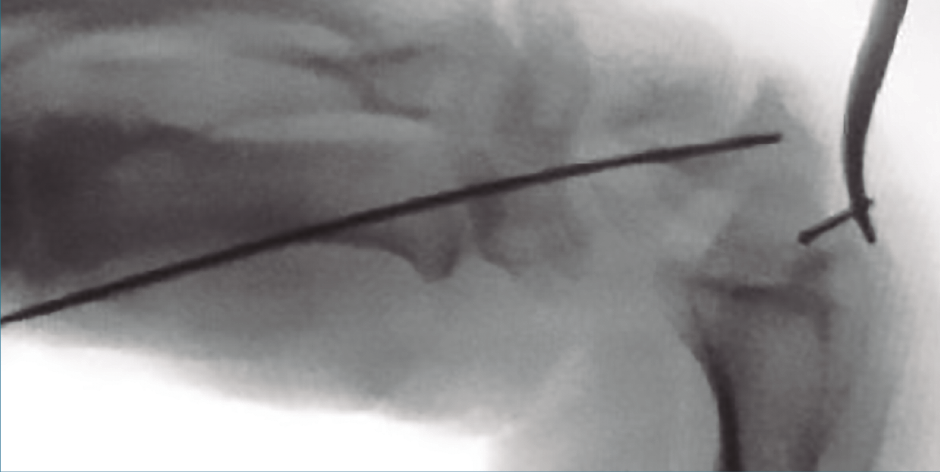

Esta técnica no está exenta de complicaciones, Bushnell(34) describe un 21% de complicaciones mayores, entre las que se incluyen la pseudoartrosis; lo más frecuente son problemas con el material de síntesis (Figura 6) e incluso una fractura postoperatoria; y una serie de complicaciones menores como la rotura intraoperatoria del tornillo o de la aguja. Las lesiones tendinosas en abordajes percutáneos puros son elevadas, oscilan entre los 5 sobre 12 y los 5 sobre 40 en función de los estudios(35,36).

Figura 6. Imagen escópica de la rotura de la aguja guía en un abordaje anterógrado.

Tal como manifiesta Bushnell(34), “las complicaciones pueden representar un problema considerable para los cirujanos y los pacientes, y los cirujanos no deben suponer que todos los pacientes tendrán excelentes resultados con un riesgo mínimo de problemas cuando se utiliza una técnica percutánea”. Debe valorarse cuidadosamente la técnica quirúrgica, por lo que se aconseja la colocación central de la aguja de Kirschner, mantener la muñeca en flexión/pronación (ring sign), colocar la aguja de dorsal a volar –la aguja debe salir en la base radial del pulgar–, debemos confirmar la reducción con fluoroscopia, es necesaria una medición cuidadosa de la longitud del tornillo, restar unos 4 mm, no brocar los últimos 2 mm de la cortical distal y considerar que la mayoría de las complicaciones son por una mala técnica quirúrgica.